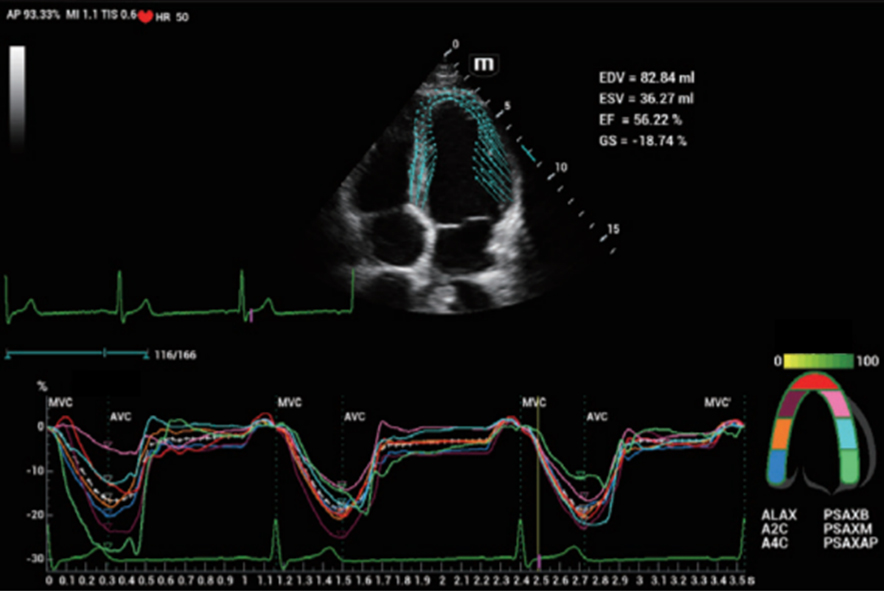

Für die Ultraschalltechnologie stellt die ZST+-Plattform einen bedeutenden Fortschritt dar, da sie statt der herkömmlichen Strahlformung die Kanaldatenverarbeitung verwendet. Diese bahnbrechende Innovation löst übliche Zielkonflikte zwischen räumlicher Auflösung, zeitlicher Auflösung und Homogenität des Gewebes auf, woraus sich eine beispiellose Bildqualität ergibt, die den Weg frei macht für unendlich viele Bildgebungslösungen.

Das Resona I8 weist vielfältige klinische Lösungen auf, die speziell für den jeweiligen Anwendungsbereich entwickelt wurden. Die Technologie baut auf einem tiefgreifenden Verständnis verschiedener klinischer Szenarien auf und bietet eine umfassende Serie fortschrittlicher Diagnoseinstrumente, beispiellose Intelligenz und präzise Analysen zur Verbesserung von Diagnosesicherheit, Qualitätskontrolle und Scaneffizienz.